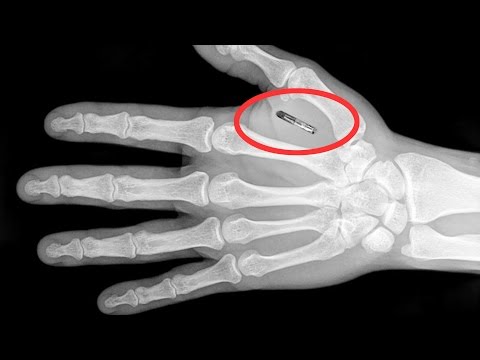

Microchipping humans may be common in the future. The prospect of constantly being tracked and online raises some major ethical concerns. Futurist and humanist Gerd Leonhard provides insight into where we're headed.